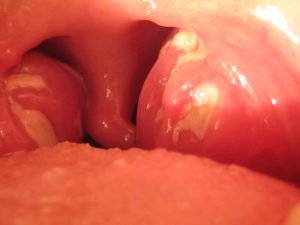

Quando NeoBorocillina non basta: la tonsillite